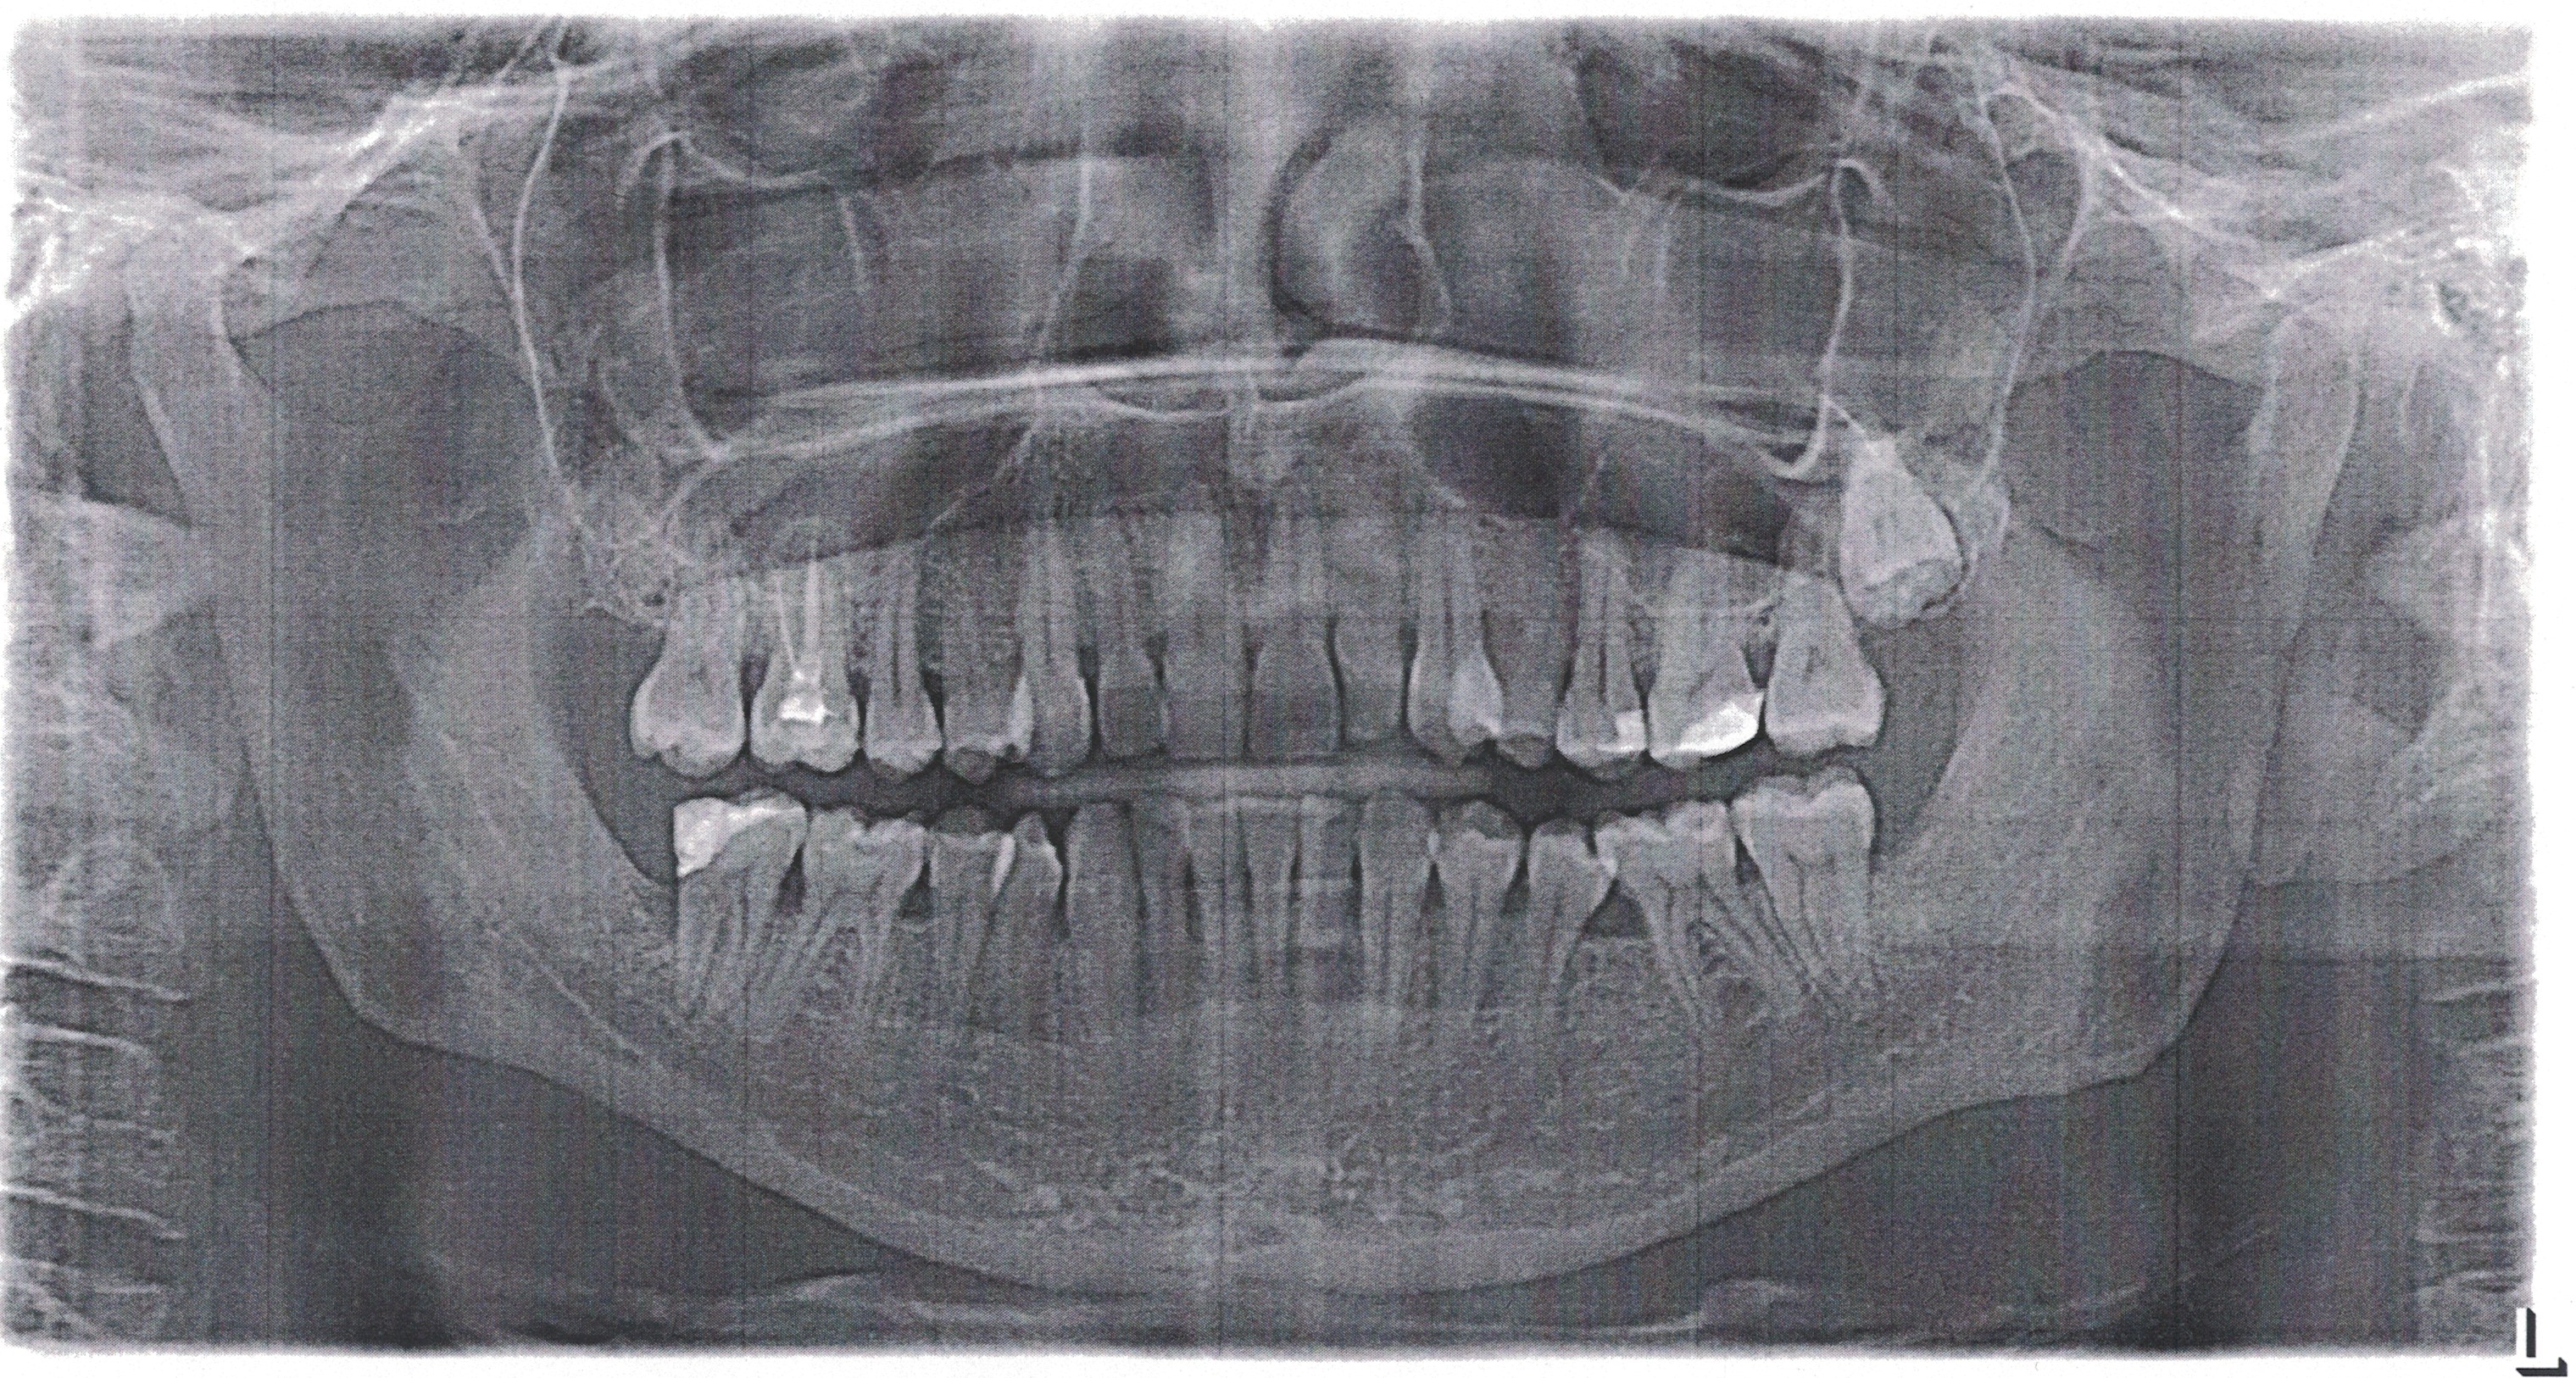

Рисунок 3 - Ортопантомограмма пациента до лечения